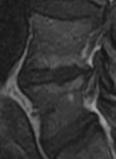

Discopathie MODIC 1: Notez le respect des corticales, la masse des parties molle antérieure en hyposignal T2 (disque extériorisé) et la prise de contraste linéaire du disque